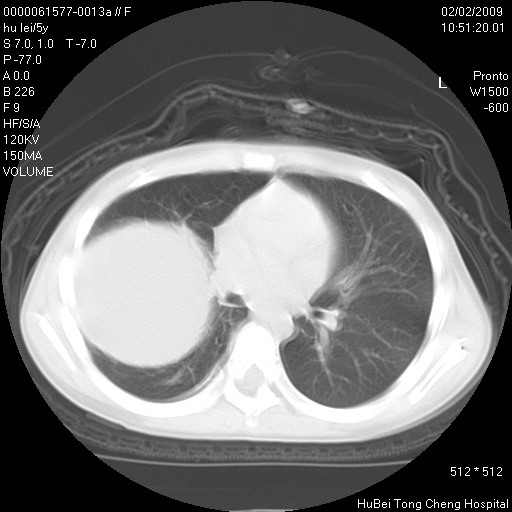

标题: PED1732:M5Y,右肺囊性占位!

患者:男,5。无明显不适,拍胸片考虑右肺囊肿。

行ct扫描,图象如下: